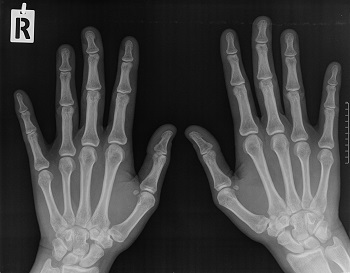

Също така ви изпращам първоначалната снимка на лявата ръка, както и снимката на двете ръце, направена преди около 2 седмици, ако може да ми кажете какво според вас е състоянието на ръцете ми и дали може да се определи дали това образувание на лявата ръка е хематом, ганглион или нещо друго.

- Img2.jpg (28.06 KiB) Прегледано 1751 пъти